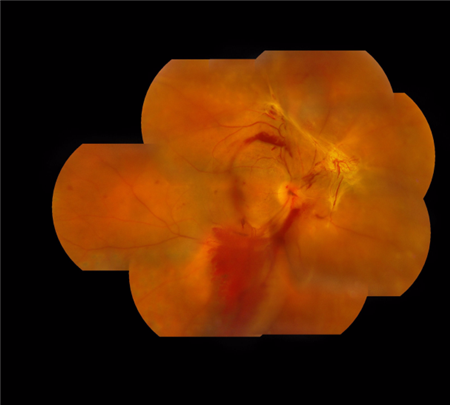

“糖网病”即糖尿病性视网膜病变,是一种比较常见的眼底病变。但由于大家对糖网病了解不深,有些患者在视力受损比较严重甚至失明的时候才去找眼科医生看病,因此耽误好了的治疗时间。

糖尿病的一个典型特征就是血糖偏高,如果血糖没有控制好,长期血糖偏高则有可能损伤血管内皮细胞,进而导致眼睛视网膜微丝血管病变,即“糖尿病性视网膜病变”。

糖尿病视网膜病变主要有三种形式可以对视力造成较为严重的影响:

黄斑水肿:由于黄斑水肿位于视网膜中央,是视力比较敏锐的位置,若因糖网病发生黄斑水肿,感光机能也会跟着受到影响。

视网膜脱落:若眼球内反复出血,便会出血疤痕化,导致视网膜变形,严重可引发视网膜脱落。

眼内出血:眼内出血即玻璃体出血,是由于新生血管破裂造成的。混浊的玻璃体使得光线通过瞳孔后被阻拦,视力自然会受到较大影响。

值得警惕的是,视网膜病变早期可以毫无征兆,直到视力损伤严重了患者才有所察觉,然而这时候已经受损的视力很难挽回。因此,糖尿病患者应更加关注自己的眼睛健康情况,如能及早发现并进行针对性治疗,视力大多能够得以保留。